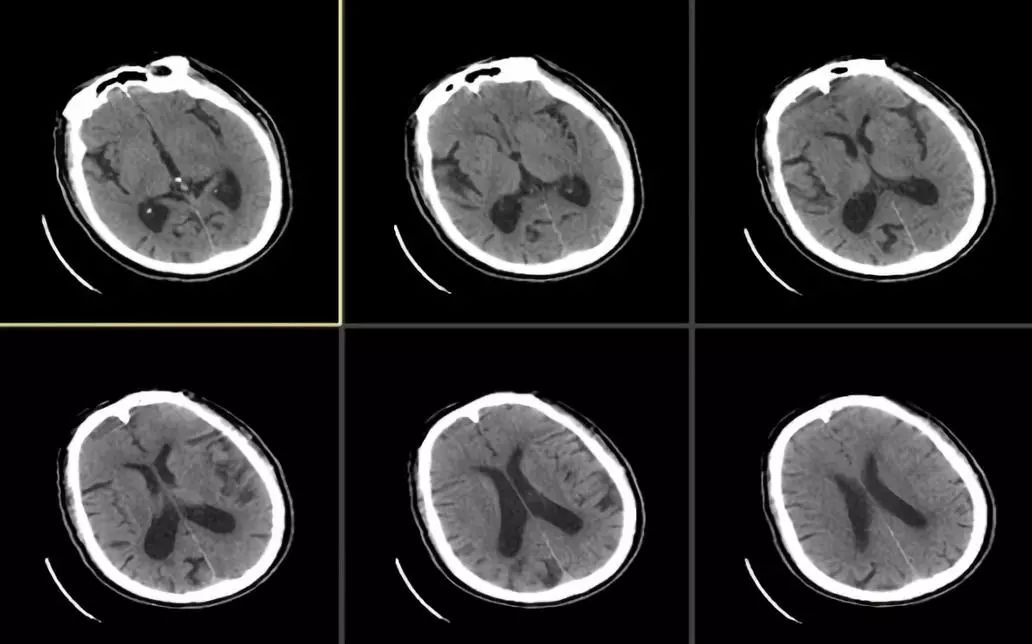

溶栓前头颅平扫CT检查未见明显新发病灶(图1),ASPECTS评分:10分

图1

溶栓后复查头颅CT检查未见出血,但左侧大脑中动脉有高密度征(图2)。

图2